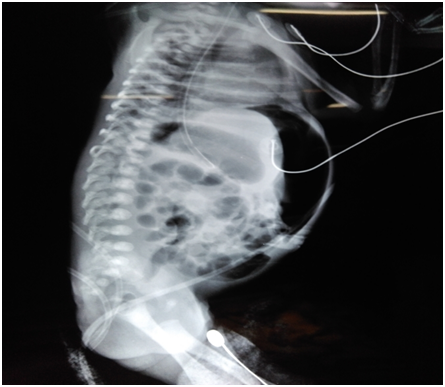

A 1.9 Kg preterm baby was born at 33 weeks gestation by LSCS for abruption placenta. Baby developed RDS and needed intubation and ventilation with administration of surfactant. She required ventilation for 7 days followed by CPAP support. Baby developed acinetobacter sepsis which was treated with appropriate antibiotics Baby was passing meconium during the first five days and had no abdominal distension though trophic feeds were not tolerated. Mild abdominal distension was noted on eighth day which was attributed to sepsis, CPAP and RDS. Baby developed constipation, followed by increase in abdominal distension and NG aspirates. A mass was noticed below the liver on 12th day and left lateral decubitus x-ray film showed Pneumoperitonium (Figure 1). At laparotomy a 5*5cms thick walled cyst firmly adherent to the under surface of the liver was seen with perforation and spillage of meconium. Small intestine loops were adherent in this area with formation of a mass. After the bowel loops were separated the hepatic flexure of colon was seen entering the cyst and exiting out distally (Figure 2). Complete excision of the cyst with involved intestine was not possible due to dense adhesions to liver. Hence the cyst was opened, wall partially excised and mucosa from the involved segment of colon inside the cyst was stripped and removed (Figure 3). Ascending colon was brought out as stoma and transverse colon as mucous fistula. Post op recovery was uneventful. At 4 months baby was admitted with adhesive obstruction and treated with laparotomy and release of adhesions. At 6 months of age baby was seen thriving well and the stoma was closed after ensuring patency of distal bowel by distal colon gram. Baby is on regular follow up, feeding well and gaining weight.

Meconium peritonitis is defined as a sterile chemical peritonitis due to leak of meconium from intestine into peritoneal cavity during intrauterine period. The perforation causing this can occur anywhere from 4th to 6th week of gestation to several hours after birth.2 The incidence is 1 in 30,000 live births.1 The proposed etiology for perforation include ischemic bowel lesions associated with mechanical obstruction like atresias, volvulus, extrinsic congenital bands, meconium ileus, internal hernias, intussusceptions, meckels diverticulum, Hirschsprungs disease and idiopathic cause.3 The mortality in the past was high as 50-60% but now reduced to less than 10%1 and mostly due to antenatal diagnosis and improved neonatal intensive care. Meconium peritonitis pseudo-cyst (MPC) accounts for 12% of meconium peritonitis.4 In our child the antenatal scan was done at 20 weeks which was normal. Baby was delivered at 33 weeks due to abruption placenta and there were no scan in between this period to know if there was an antenatal event. When we reviewed the X rays taken for ARDS, X ray on day 1 and 2, abdomen appeared normal but on day 3 of life there were signs of free air in peritoneum which was missed. Baby was passing meconium normally for first 5 days and associated sepsis and ARDS obscured the early diagnosis for our baby. Though X ray showed features of Pneumoperitonium on day 3 the overt signs of peritonitis like bilious aspirates and abdominal distension appeared much later on day 12. The clinical progression to peritonitis might be slow probably because, the gut continuity was maintained with no distal obstruction and use of broad spectrum antibiotic for treatment of sepsis. Our intra operative findings confirmed a ruptured meconium pseudocyst (Figure 3). We could not find any underlying etiology as there was no evidence of atresia. Meconium ileus and Hirschsprungs disease was ruled out based on clinical course and meconium history and colonic biopsy. Ileal atresia, volvulus and idiopathic are the most common causes and meconium illus is more common cause in Caucasian population.